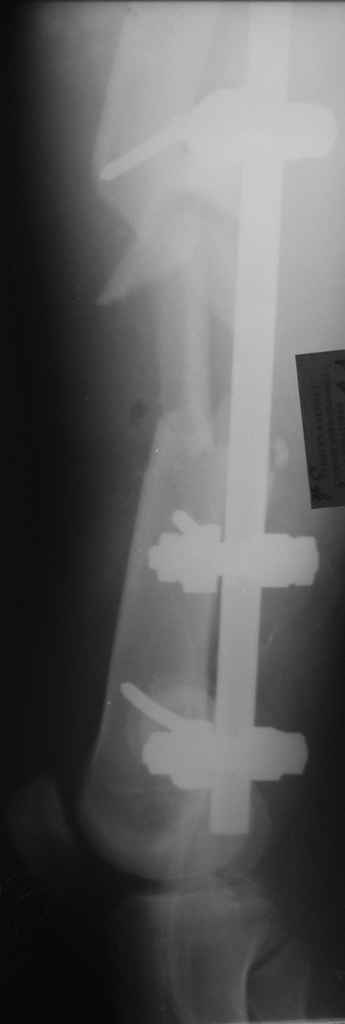

Больной 29 л 23 февраля на мопеде въехал в легковой автомобиль (естественно, больной пьяный). Поступил с диагнозом: закрытый перелом правого бедра в с/з-н/з, открытый перелом правой голени в в/з (рана в проекции перелома до 3 см), открытый оскольчатый перелом левого бедра в с/з с дефектом костной ткани (рана до 12 см по наповерхности бедра). ПО дежурству - ПХО ран, стержневые аппараты на оба бедра, аппарат Илизарова на правую голень. По стабилизации состояния - домонтаж аппарата Илизарова с окончательной репозицией. Спустя 2 недели - открытая репозиция отломков правого бедра, интрамедуллярный остеосинтез стержнем с дистальным блокированием. С правой ногой разобрались. Вопрос встает о том что делать с левой. При ревизии раны левого бедра (при поступлении) удален торчащий из раны свободный осколок до 6х3 см,загрязненный травой,пылью.Со слов скорой - на месте происшествия вроде как были еще мелкие костные осколки. Осколки что на снимке лежат по внутренней поверхности бедра, связаны с м/тканями, дефект кости до 7-8 см по длине. Массы осколков явно не хватает для его заполнения. Кроме того массивное скелетирование основных отломков (до 7-10 см в обе стороны). Все раны зажили без проблем. Наши планы - открытая репозиция левого бедра, ИМО с укорочением. Потом когда (если)срастется пусть занимаются реконструктивными операциями. Буду рад услышать ваши мнения, предложения по данному случаю.С уважением А. В. Л.

Вчера сделали снимки - положение отломков и осколков вот такое. На перевязке: из раны небольшое кол-во сгустков крови с примесью гноя , хотя бедро спокойное, гипертермии ни локальной ни общей нет. Вопрос: как быть дальше? открывать рану, "чистить" ее, наладить ее перфузию АС, АБ? что делать с осколками, попробовать перекрыть область перелома с фиксацией основных отломков аппаратом. Или осколки убрать и состыковать основные отломки с жутким укорочением и большими проблемами при зашивании раны?